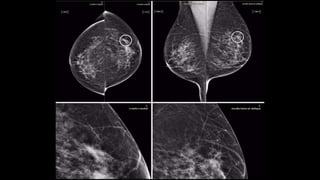

• Mamografía

• Rx localizada (0.3 rad) screening y diagnóstico de ca en etapas tempranas

• Identifica lesiones <de 100 µm, se complementa con magnificación

• Screening ACS: anual desdelos45 años

• Escasautilidaden<40 años.

• Tomosíntesis

• Mx demúltiplesimgparalelasde1mm

• Evaluacióndelesión-lesionesporcapas

• Mejordiagnóstico,inclusoenlesionesincipientes